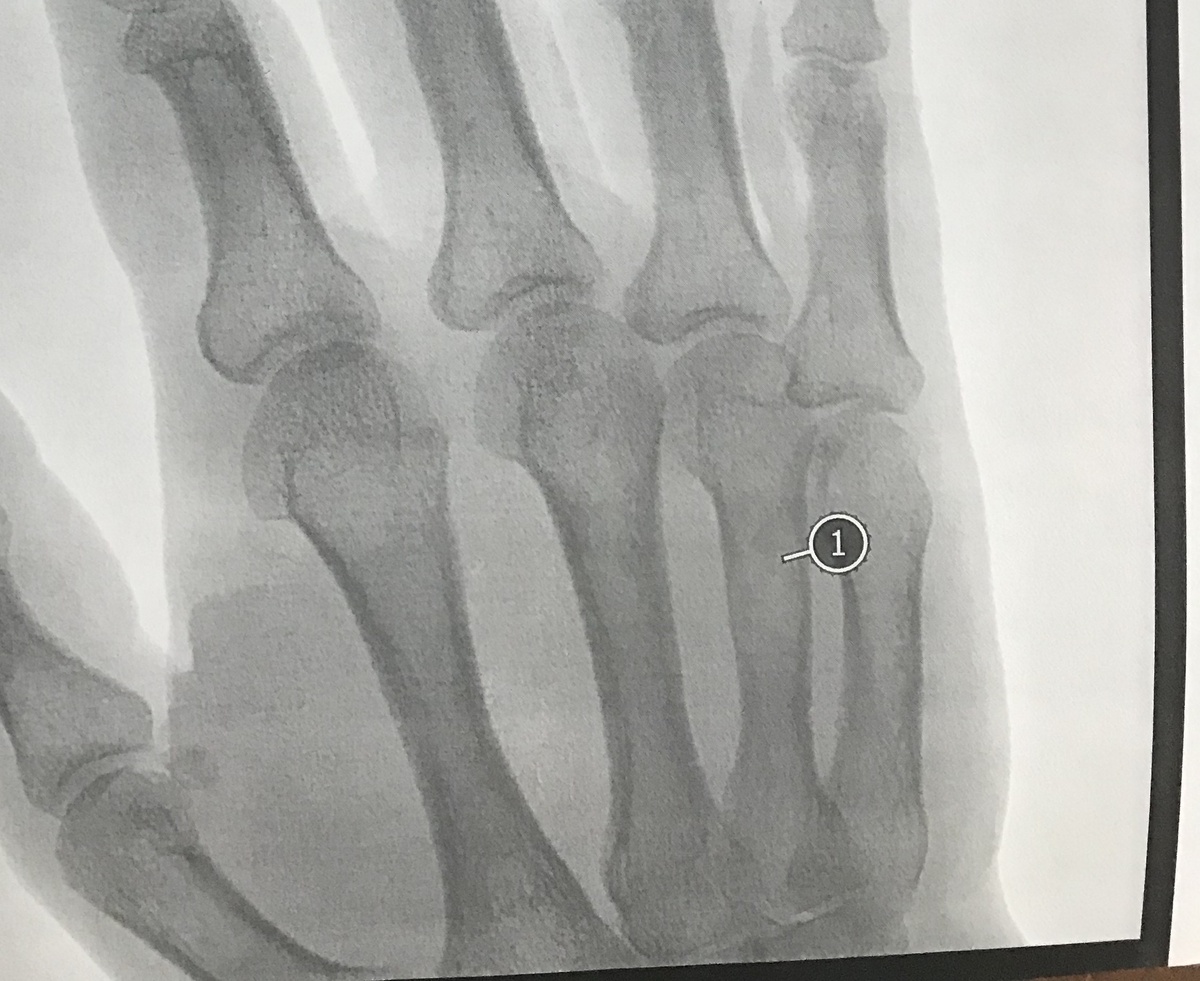

Перелом и восстановление шваброй по совету врача

В одной из статеек я рассказывала, что сломала пястную кость правой руки...